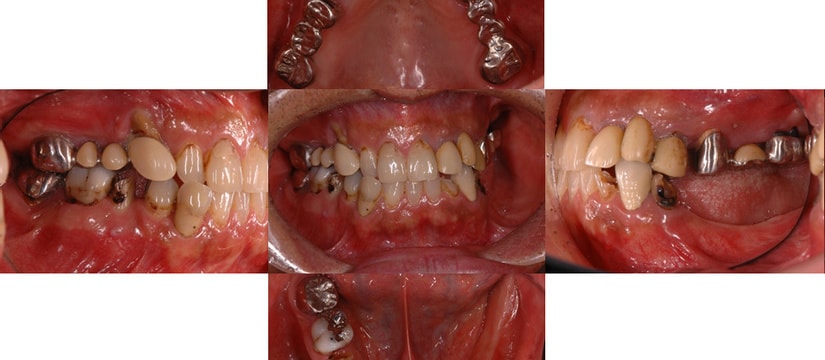

かみ合わせが崩れてしまった場合

治療前のかみ合わせのままで治療しても長持ちしないこと、本来のかみ合わせから崩れてしまっていると判断し、お口の中を総合的に治療する治療方法を提案させていただき治療を行いました。

治療前

咬むと前歯が痛いと来院された患者さん。奥歯がないため、前歯に負担がかかり、下の歯がないまま放置していたため、上の歯が下に下がってしまうなど様々な問題をお口の中に抱えていました。

残すことが出来ない歯の抜歯などを行うと、すれ違い咬合という治療するには難しいかみ合わせであったことなど、仮の入れ歯などで咬合状態の経過観察などを行ったため治療期間は約2年ほどかかりました。